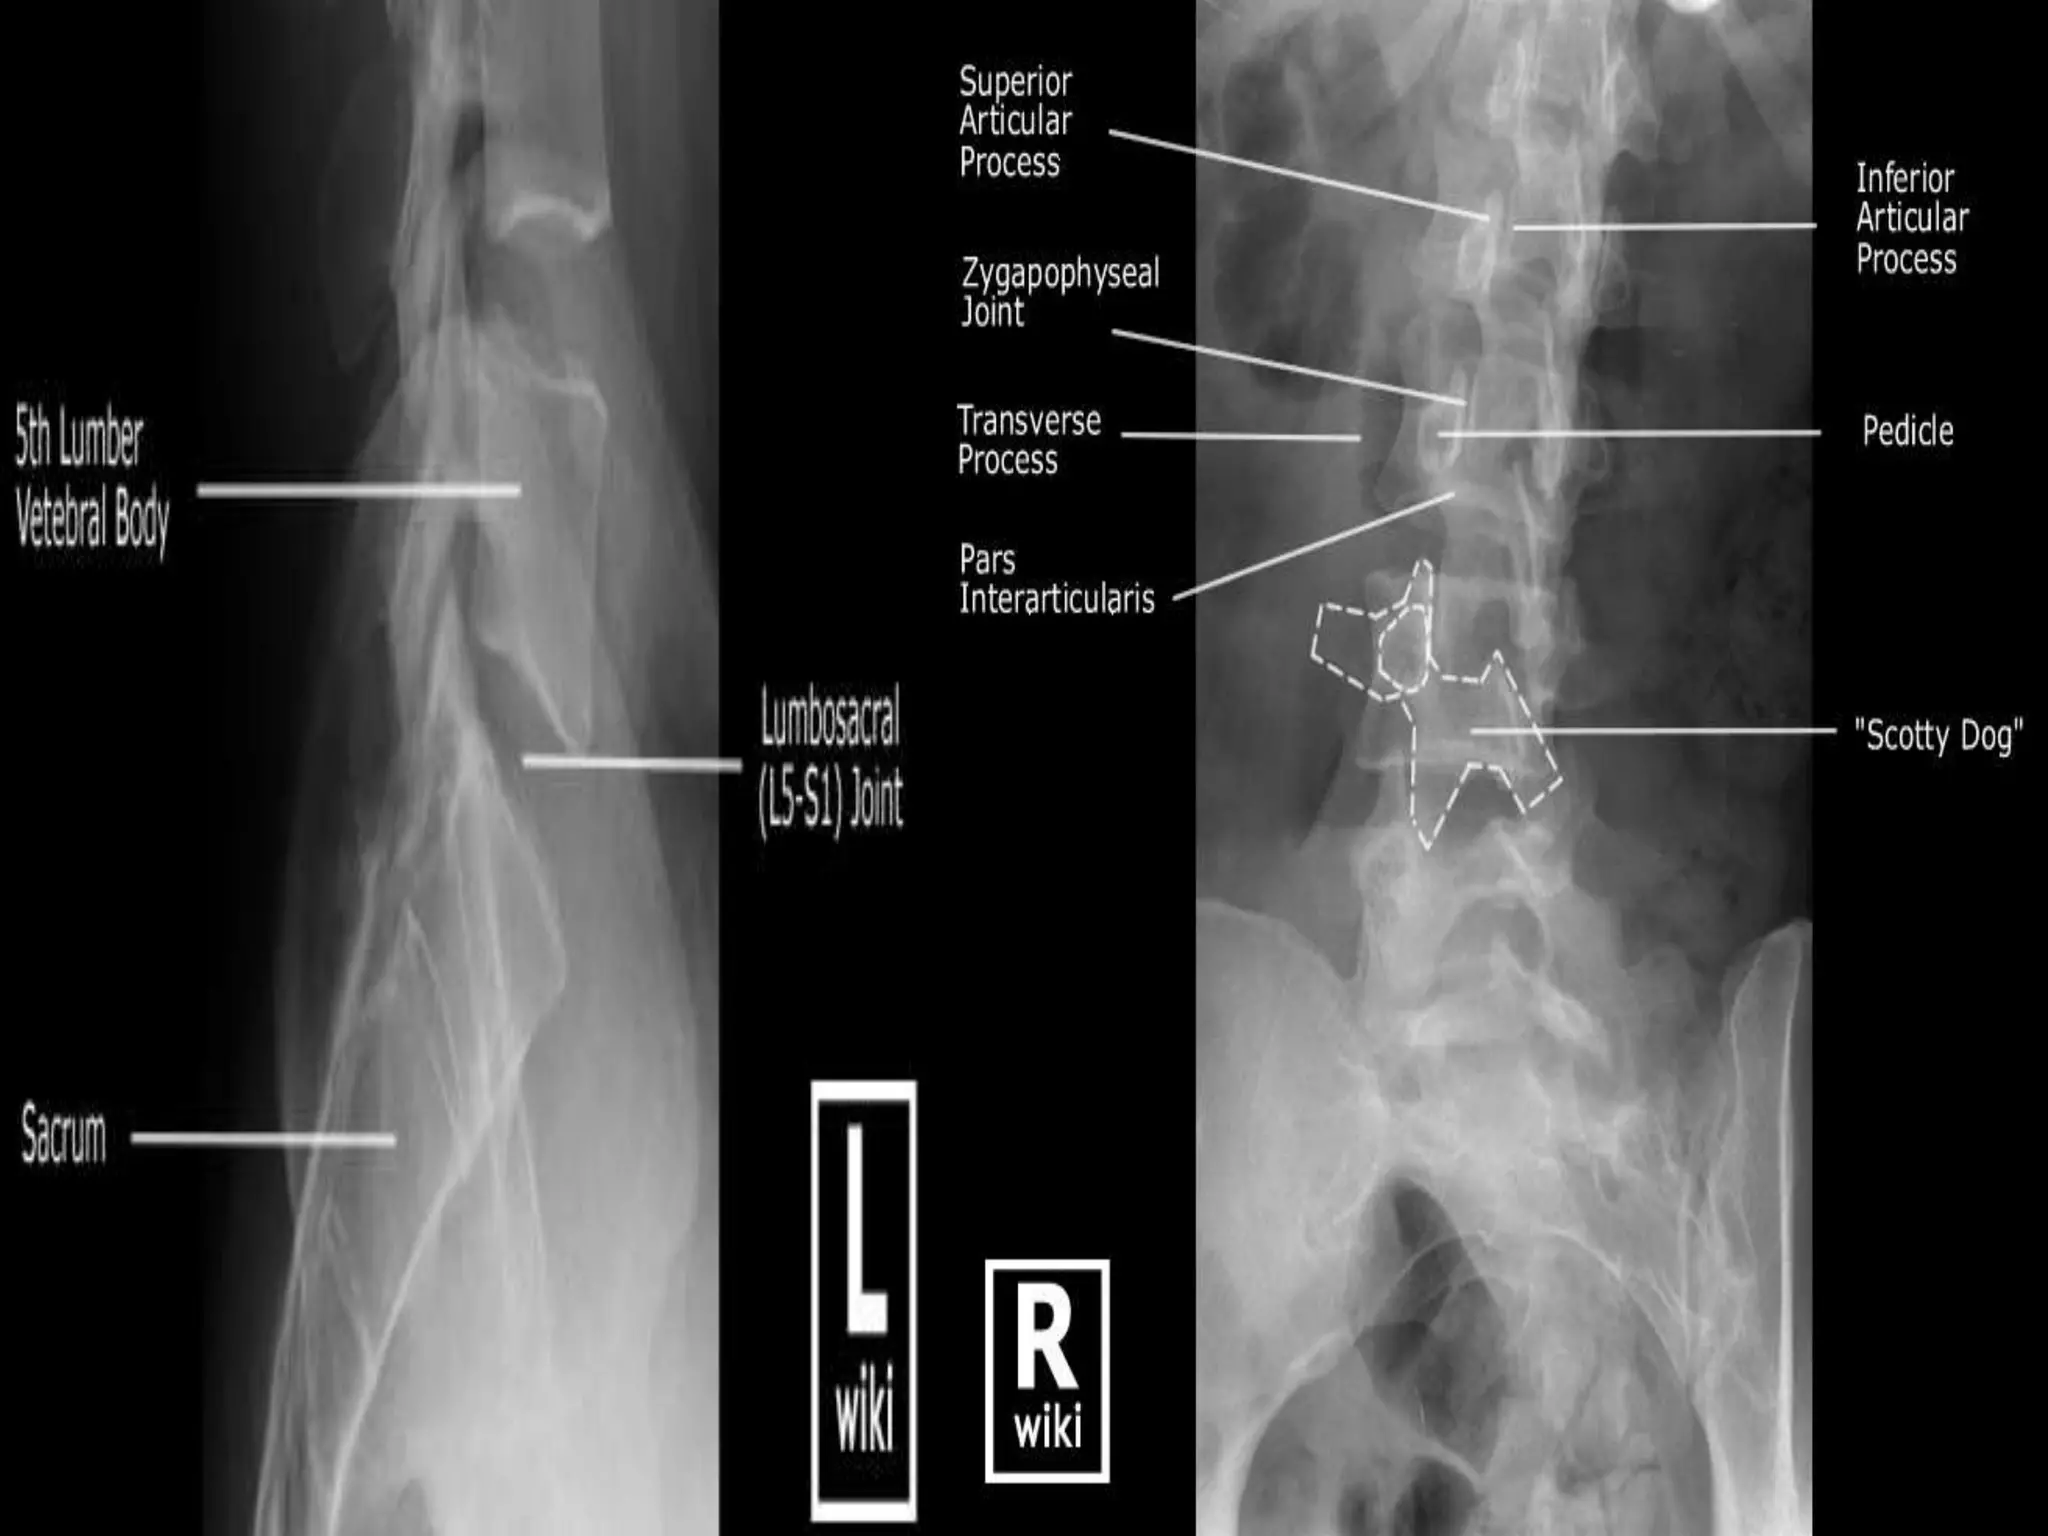

L.S. Spine.

Oblique Views.